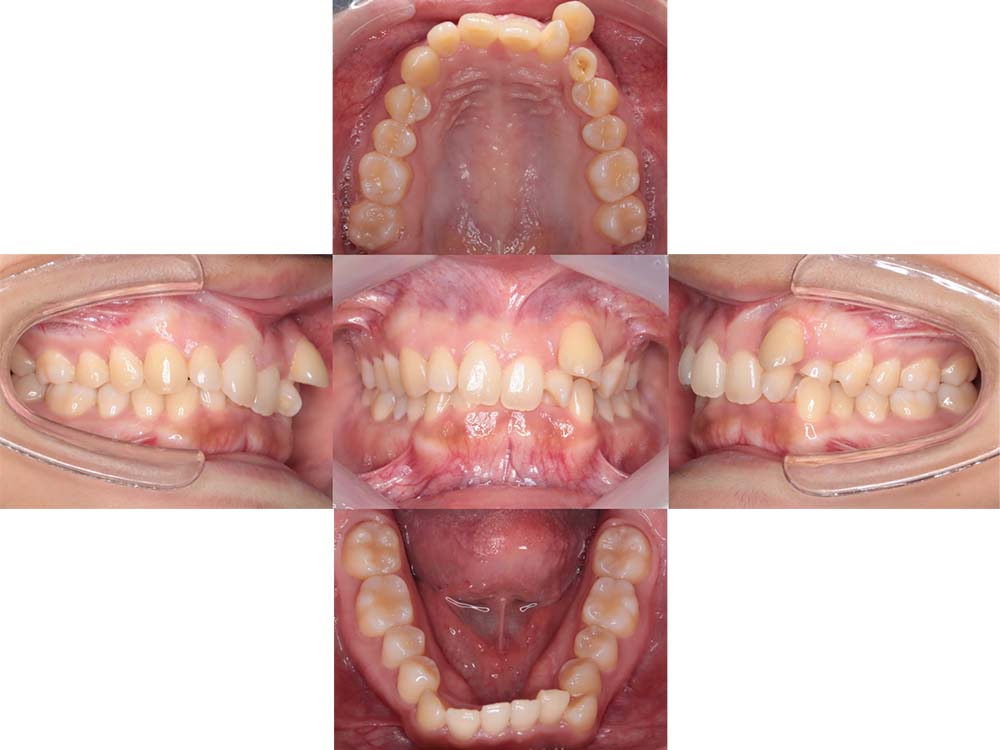

症例01

| 主訴 | 歯並びがガタガタしている。 |

| 診断名あるいは主な症状 | 叢生 |

| 年齢/性別 | 22歳・男性 |

| 矯正ステージ | 大人の矯正治療 |

| 治療方法 | ワイヤー矯正 |

| 抜歯部位/抜歯有無 | 非抜歯 |

| 治療内容 | 上顎大臼歯の遠心移動により前歯のガタガタを排列スペースを獲得し全顎的な排列を行った。 |

| 費用 | 85万円程度(2025.10時点の料金となります。) ※矯正基本料金、審美ブラケットを含む |

| 治療期間 | 2年4ヶ月 |

| 主なリスク・副作用 | 痛み、歯根吸収、歯肉退縮、虫歯、後戻り |